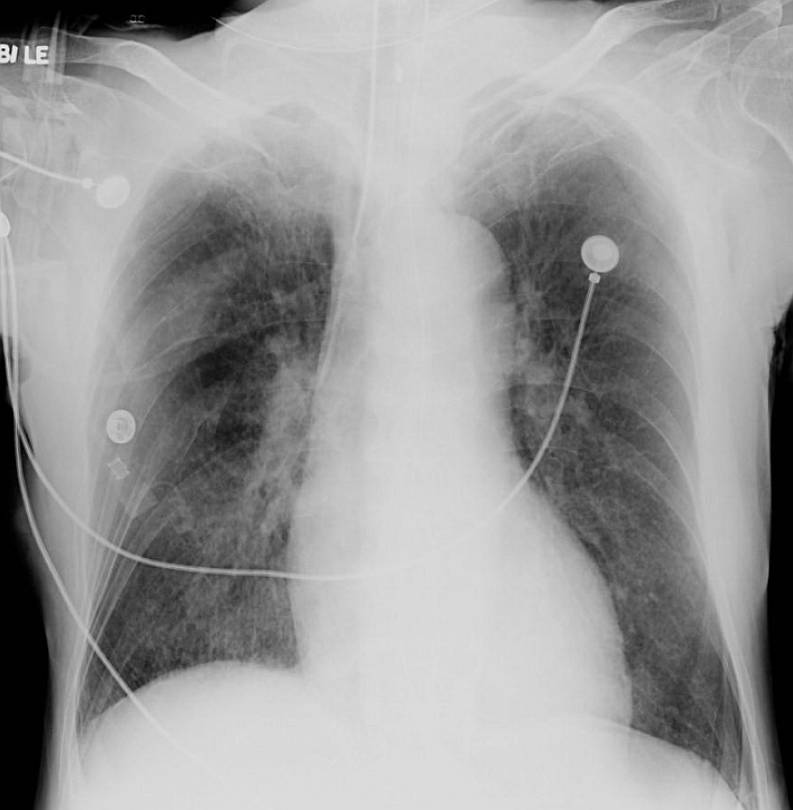

A chest radiograph was obtained at the time of admission showing bilateral upper zonal opacification, with no obvious Kerley B lines or pleural effusions.

Although NPE can present with variable appearances on chest radiographs, unilateral or asymmetric bilateral upper zonal lung involvement is a known classic presentation. In contrast to the garden variety cardiogenic pulmonary oedema, features such as Kerely B lines and pleural effusions are usually absent.